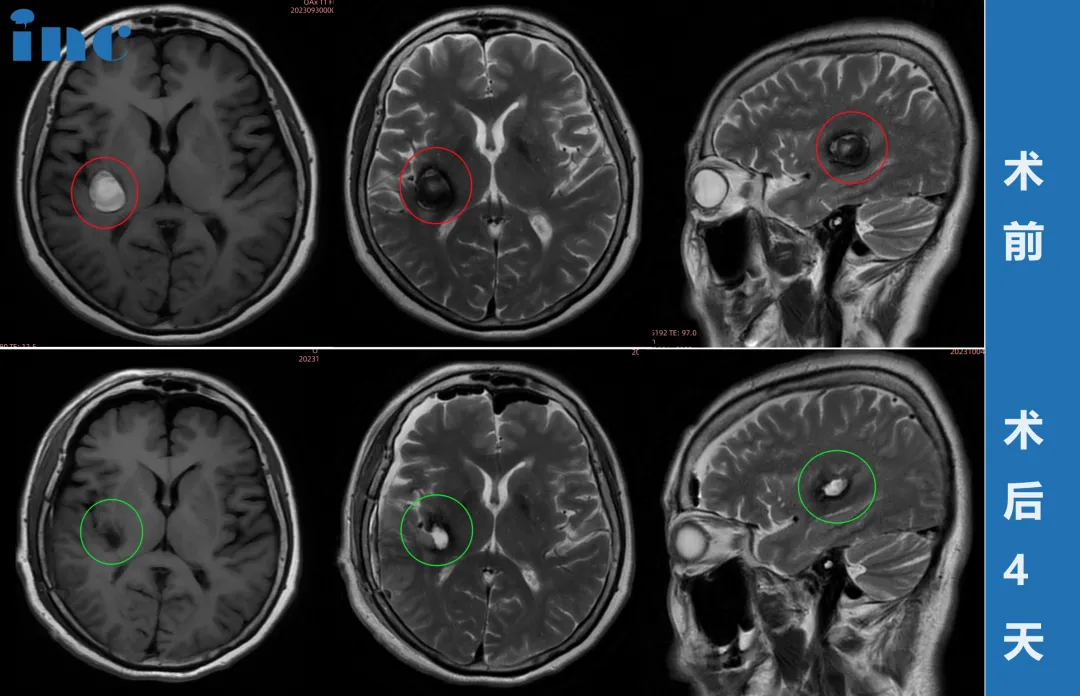

然而,疾病这个东西有的时候真是无法预料。2023年9月,柯女士的症状突然加重:脚底麻木蔓延至膝盖,脸部、耳朵也出现麻胀疼痛,复查核磁显示病灶已增大。

巴教授的这份责任与担当打消了柯女士和家人所有顾虑。9月29日视频咨询,30日柯女士从东北飞赴苏州,10月1日——国庆节当天,由巴教授主刀,国内神经外科团队精密配合下,为她成功手术。术后核磁显示,海绵状血管瘤已完全切除,且没有新的神经功能损伤。

术前,巴教授曾告知最坏情况可能是左手无力,这让柯女士在术后醒来的第一时间就下意识活动左手——当感受到手指灵活时,她悬着的心彻底放下。更令人惊喜的是,教授担心的高龄患者常见脑萎缩问题并未在她身上出现,脑部状态甚至优于同龄人,这也为手术成功提供了有利条件。